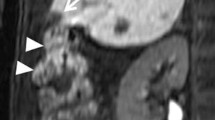

All patients underwent pretreatment blood chemistry testing and imaging evaluation. We considered total and fractionated bilirubin, Quick’s time, INR, albumin, platelets, ammonia, α-fetoprotein (αFP), and ferritin and hepatitic markers. We obtained an ECG for each patient. Before the cryoablation procedure all patients also underwent upper abdominal US imaging (ATL HD 5000; Philips, Best, Netherlands) and 64-multislice CT scan (LightSpeed 64 CT; GE Medical Systems, Milwaukee, WI, USA) with the three-phase technique (30, 65, and 180 s) following intravenous injection of a 120 ml bolus of iodinated contrast medium (300 mgI/ml; Ultravist, Schering) and a 20 ml bolus of physiologic solution (Figs. 1 and 2). Scanning parameters were 1 s gantry rotation time, 1.25 mm collimation with the possibility of retroreconstruction at 0.6 mm, 360 mA, and 120 kV.

Contrast medium was injected at a rate of 2.5–3 ml/s through an 18 G intravenous catheter inserted in an antecubital vein. Each patient was treated after local injection of 10 ml lidocaine (2%). After sonographically determining the most favorable percutanous approach, we inserted two or three cryoprobes (17 G, 14 cm long; Galil Medical, Yokneam, Israel) into the tumor under US guidance and advanced the tip to reach the distal margin of the targeted lesion. The HCCs were well and simply visualized without the use of contrast media. Cryoprobe positions were determined according to tumor geometry and expected iceball size. CT was used to verify placement of the multiple cryoprobes (Fig. 3). Each cryoprobe was equipped with a thermocouple that monitored needle-tip temperature throughout freezing and thawing. A computer interface displayed needle-tip temperatures and could be used to input the desired temperature during the procedure. Heat exchange occurred along only a 4 cm long segment at the distal end of each cryoneedle. The system consisted of a computer workstation, a gas gauge, a gas distribution system, and accessories that included needle-like cryoprobes, temperature sensors, and a remote control device. It used a high-pressure cooling gas (argon), which achieved temperatures as low as −185°C at the tip of the needle probes. The argon was converted to cold low-pressure liquid using the joule effect. To thaw the tissues a high-pressure gas (helium) was converted to a warm low-pressure gas.

Each lesion received a treatment cycle of freezing (−60°C), heating (up to 70°C), and refreezing to avoid tumor cell seeding and the duration of the procedure was based on growth of the iceball relative to the tumor (mean, 15 min; range, 10–18 min). Limited unenhanced CT scans were obtained approximately every 3 min during the first freezing time using 1.25 mm collimation to monitor growth of the iceball. CT was used to accurately monitor iceball size and location and help predict subsequent cell death (Figs. 4 and 5) [16, 17]. We used a single cycle (formed by freezing-heating-freezing) because we wanted to demonstrate the efficacy of single and short-time treatment in accordance with in vitro studies by Tacke et al. who observed no differences in maximum diameter among three freezing cycles that were performed at different locations in the same liver with direct visual measurement [14].

Our initial experience was treating four patients with HCC. The maximum diameter of the four lesions ranged from 1.8 to 3 cm. Cryoablation was technically successful in all patients at the end of the procedure. No repeat treatment was needed because there was no contrast enhancement in postprocedural CT control, as the diameters of the iceballs obtained ranged from 3 to 4 cm with an extension of the iceball 5 mm beyond the tumor margin in all cases. Each HCC received a treatment cycle of freezing, heating, and refreezing; and the duration of the procedure was based on growth of the iceball relative to the tumor (mean, 15 min; range, 10–18 min). The number of cryoprobes used during ablation was two or three on the basis of tumor diameter. The iceball Hounsfield unit (HU) value was 18–22, obtained with a region of interest of 2 mm localized in the area between the frozen/unfrozen edge and the cryoprobe.

No deaths or major complications (no hemorrage found in any case) occurred during the procedures, and no cases of neoplastic seeding have been observed to date. During follow-up two patients developed disease recurrence. One patient developed local tumor progression visualized as perilesional contrast enhancement at first CT follow-up control at 1 month (Fig. 7). The same patient was subjected to surgical resection of another HCC lesion 2 years previously and to RFA 1 year previously. The second patient developed a new HCC that was detected 6 months after the procedure. No local tumor or new lesions were found in the other 2 patients.